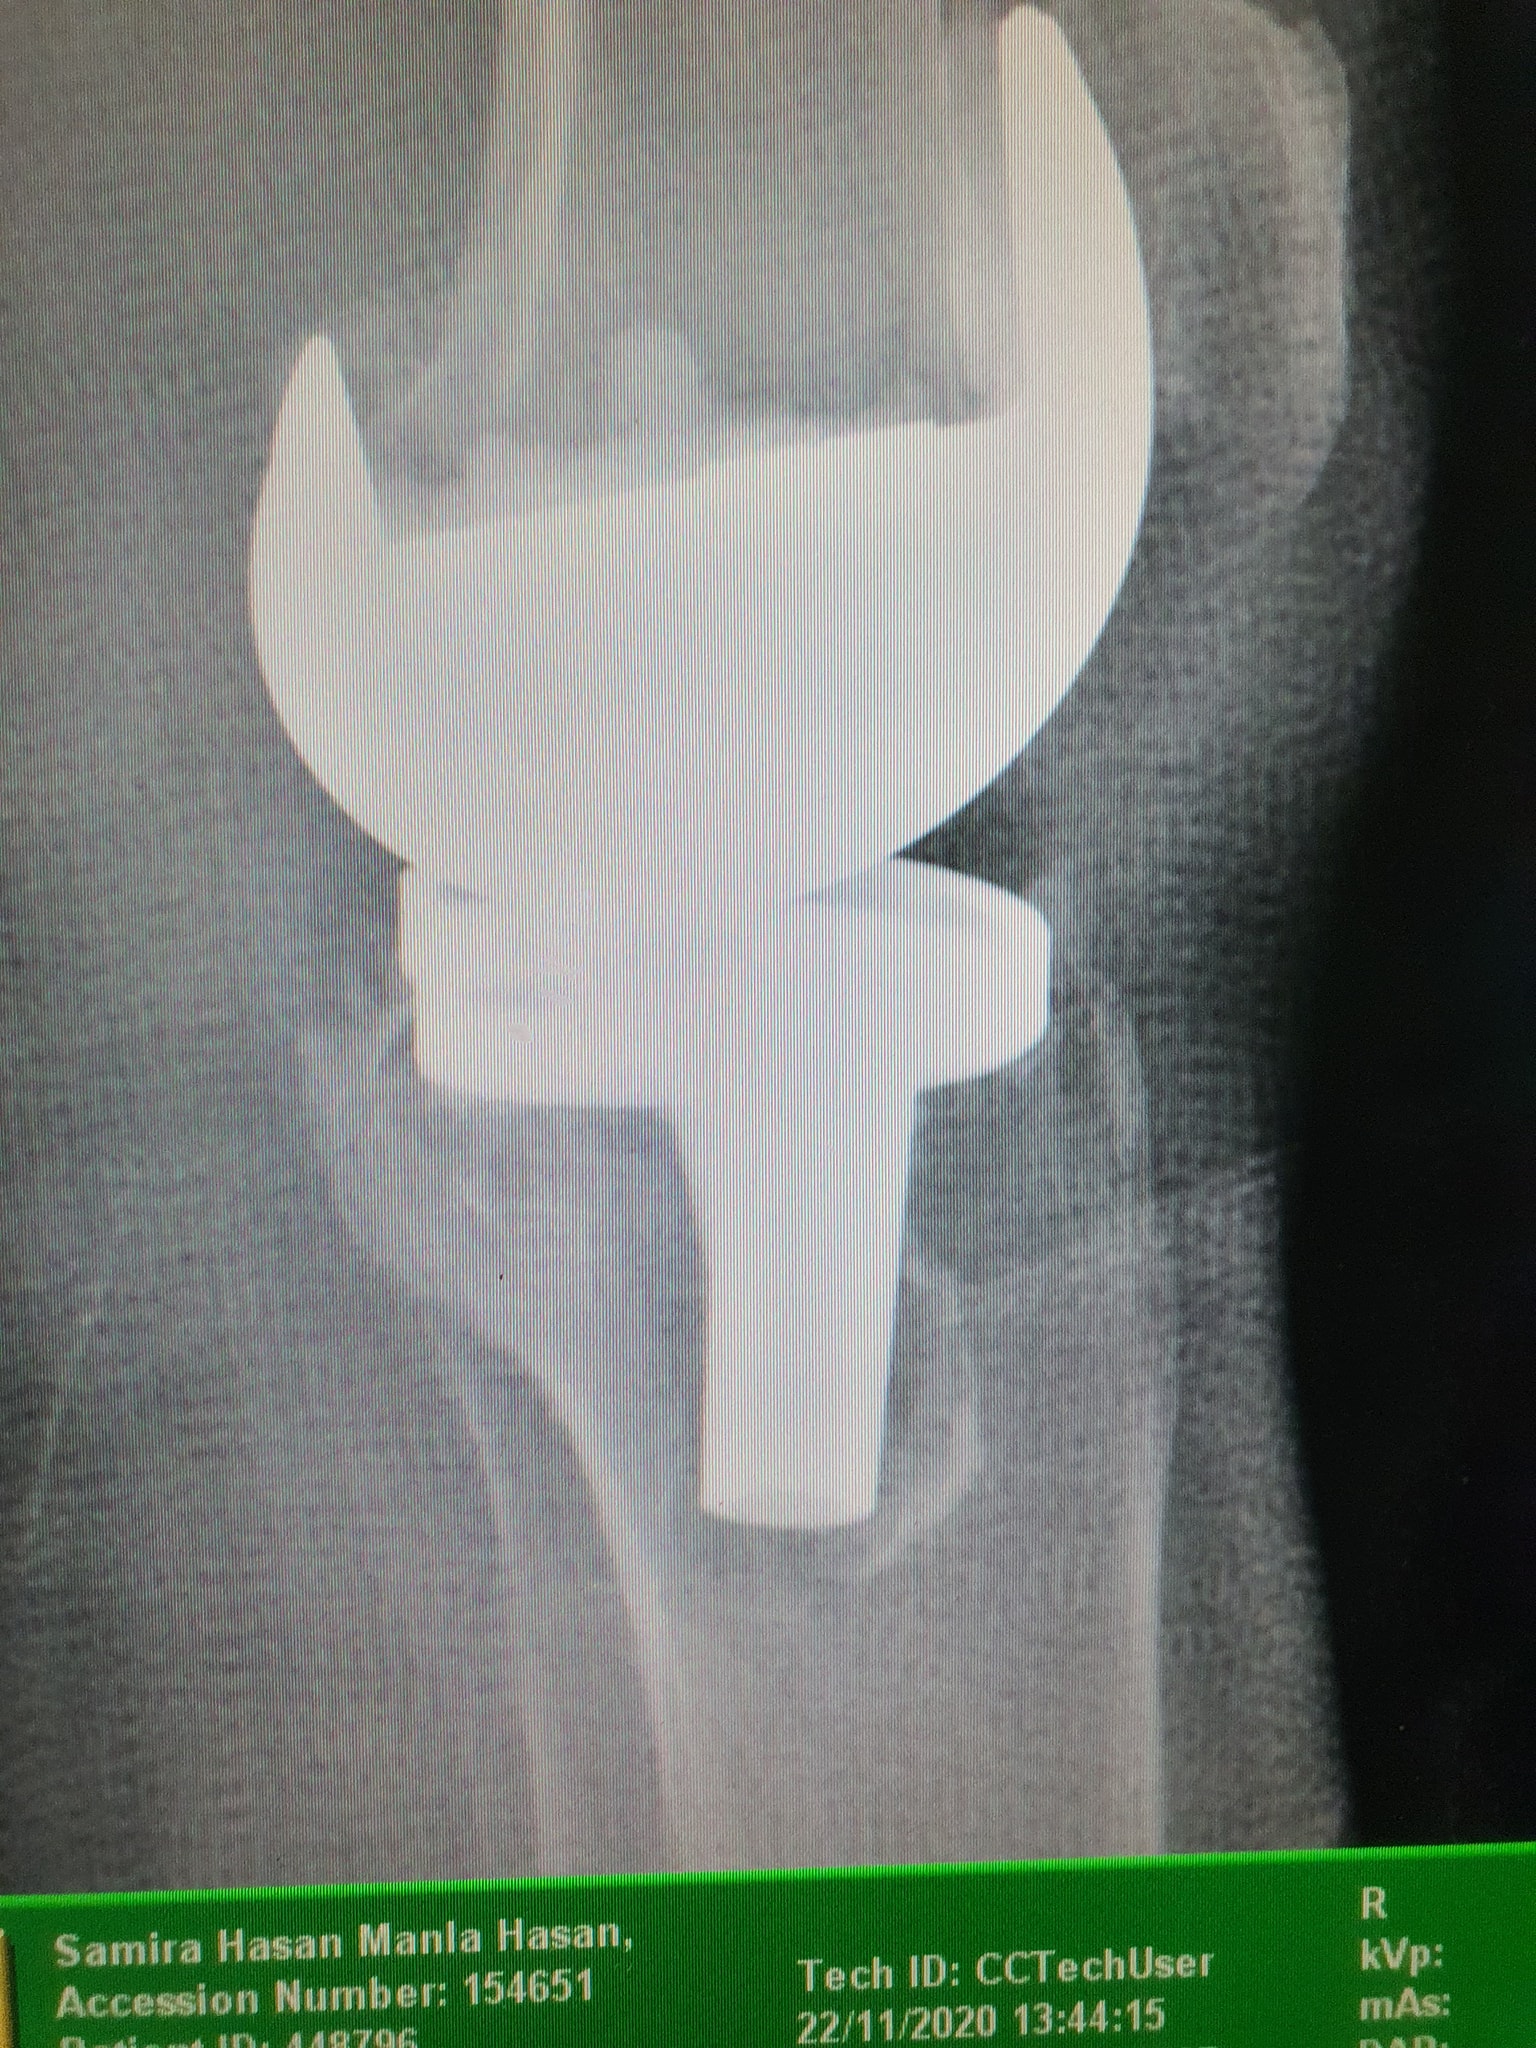

زراعة المفاصل الصناعية ورك و